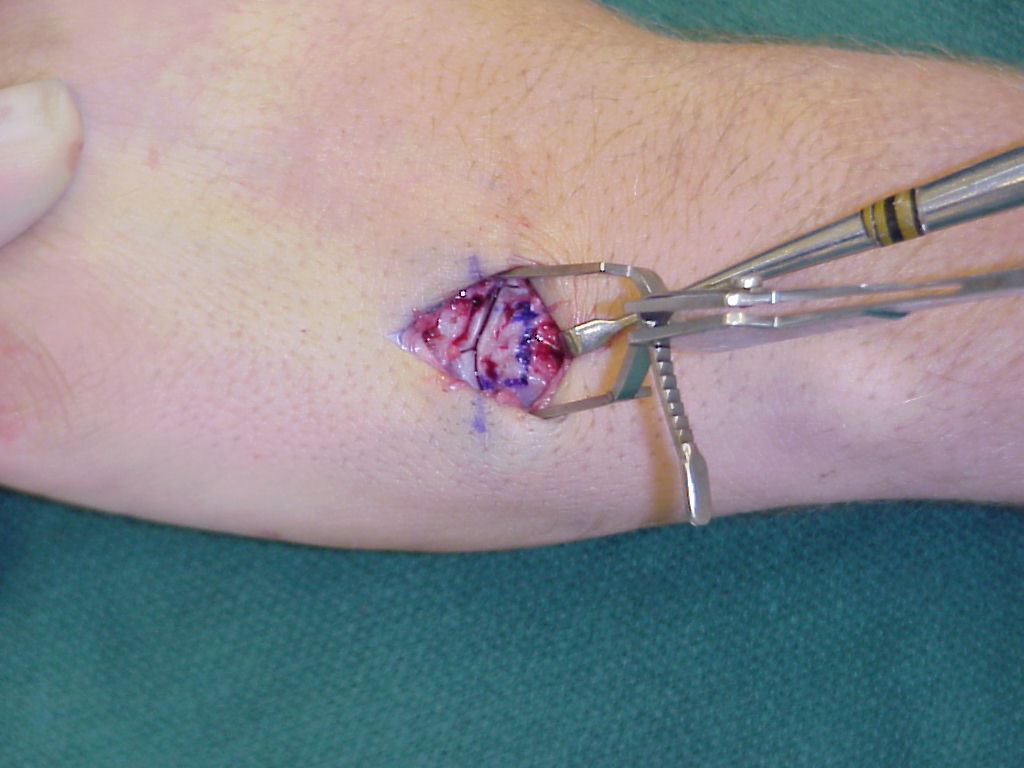

Operative approach, similar to the exposure for a volar plate arthroplasty:

Shotgun view of the pathology: the dorsal half of the base of the middle phalanx appears preserved, the palmar half recessed and covered with scar: